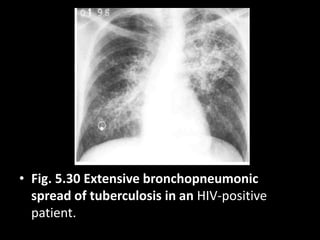

• Fig. 5.30 Extensive bronchopneumonic

spread of tuberculosis in an HIV-positive

patient.

• Fig. 5.30Extensive bronchopneumonic spread of tuberculosis in an HIV-positive patient.